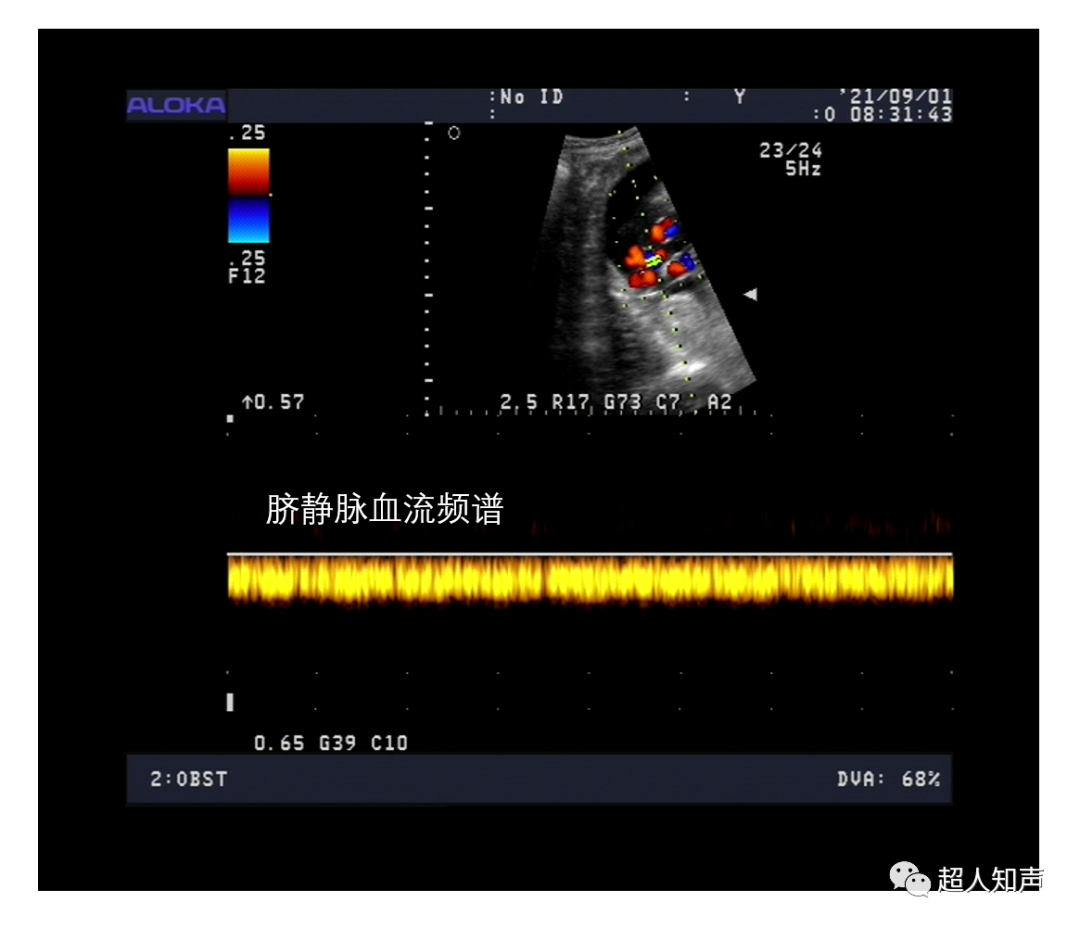

4、静脉血流 呈连续的、有或无起伏的曲线(是由于呼吸时静脉压力变化所致)。频谱信号音呈连续的吹风样或大风过境样声音。